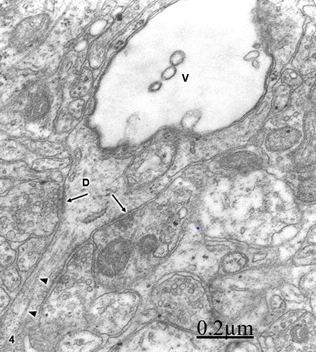

We have reported synaptic plasticity and synaptic degenerative changes of cortical axodendritic and axosomatic synapses (Figure 13).27,28 The synaptic degeneration is characterized by swollen of pre- and postsynaptic endings, coalescence presynaptic vesicles and filamentous hypertrophy (Figures 14&15).28

Figure 13 Brain traumas, subdural hematoma. Synaptic plasticity The pre- and postsynaptic membranes displayed an undulated course. The short arrows indicate the postsynaptic density. The circle shows the disrupted postsynaptic cytoskeleton. The postsynaptic endoplasmic reticulum (ER) profile appears enlarged. The long arrow indicates the fragmented limiting plasma membrane of postsynaptic ending.